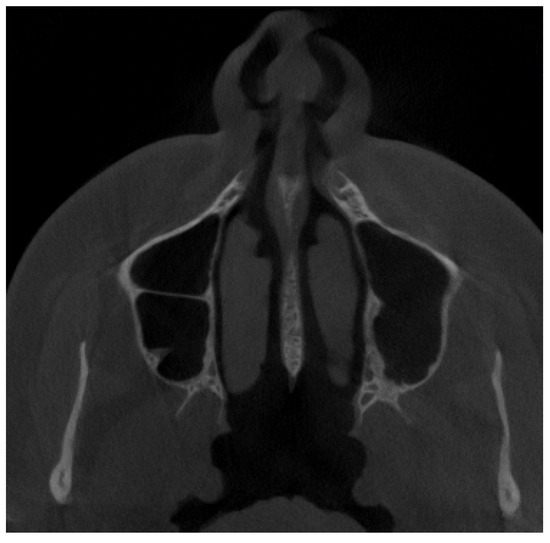

2.3. Methods—Classification Proposal

3.2. Classification Proposal